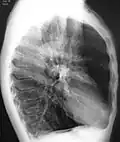

A CT scan is not routinely used except for the exclusion of bronchiectasis.[5] Pulse oximetry measurement of peripheral oxygen saturation is recommended in people with clinical signs of respiratory failure or right heart failure.[5] An analysis of arterial blood is recommended in those with a peripheral oxygen saturation of 92% or less to determine actual blood oxygen level and assess for high levels of carbon dioxide in the blood, which may have therapeutic implications such as need for non-invasive ventilation or oxygen supplementation.[10] WHO recommends that all those diagnosed with COPD be screened for alpha-1 antitrypsin deficiency.[40]

A severe case of bullous emphysema -

Axial CT image of the lung of a person with end-stage bullous emphysema -

Very severe emphysema with lung cancer on the left (CT scan)